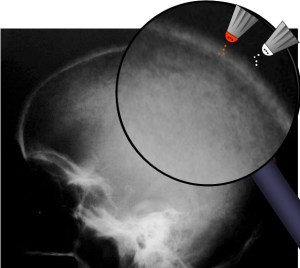

SIGNO DEL ALGODÓN

El signo del algodón hace referencia al aspecto que tiene el hueso en la radiografía de cráneo en pacientes con enfermedad de Paget. Se observa un engrosamiento de la calota en la que existen focos de esclerosis parcheados y de aspecto borroso que resaltan sobre un hueso de menor densidad.

Corte axial de TC de cráneo del mismo paciente, visto en ventana de hueso, que muestra el marcado engrosamiento del hueso y el aspecto algodonoso.